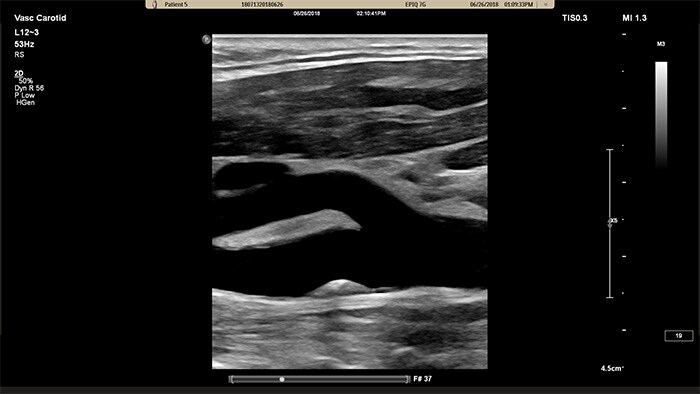

El transductor XL14-3 xMATRIX ofrece una adquisición de imágenes xPlane que supera al sistema convencional para exploraciones vasculares, pues ofrece imágenes en tiempo real tanto en los planos longitudinal como transversal de forma simultánea. La ventaja principal: las imágenes xPlane eliminan la necesidad de girar el transductor para adquirir vistas ortogonales. Basta con mover la esfera para realizar una evaluación anatómica completa, con lo que se ahorra tiempo en la exploración.